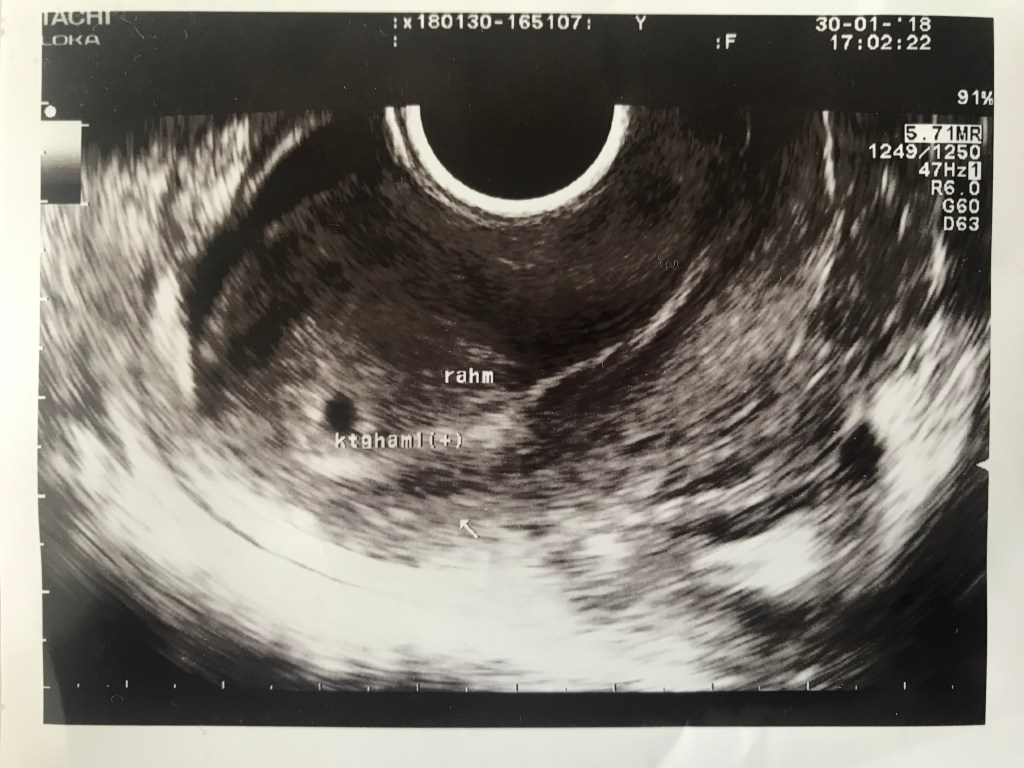

Dokter Kochhar, mengatakan bahwa diagnosanya sesuai dengan hasil laboratorium. Bahwa Nurul positif mengalami hiperprolaktin. Kadar prolaktin normal pada wanita dewasa yang tidak hamil adalah 106 sampai 850 mIU/L. Sedangkan Nurul ada pada level 4228 mIU/L. Ada banyak sebab penyebab kasus ini. Namun yang paling berbahaya adalah apabila hal ini dipicu oleh adanya microprolactinoma di otak. Semacam tumor kecil, yang membuat otak memberikan stimulus untuk memproduksu prolaktin secara berlebih. Untuk memastikannya dibutuhkan analisis Magnetic Resonance Imaging (MRI). Otak Nurul harus discan. Sembari menunggu waktu MRI, kami diminta menebus obat di farmasi. Obat tersebut bernama cabergoline. Tujuannya adalah untuk menurunkan hormon prolaktin. Dan lagi, kami diminta untuk menunggu surat dari Rumah Sakit yang berisi kapan kami bisa melakukan scan.

Awal bulan November 2017, saya kembali ke aktifitas kantor. Dan awal Desember 2017, Nurul menyusul saya ke Surabaya. Seorang teman mengatakan bahwa ada surat untuk Nurul dari rumah sakit. Surat itu dibawa oleh teman kami yang melanjutkan sewa rumah kami di Manchester dalam perjalanan pulangnya ke Indonesia. Dan benar surat itu dari rumah sakit, benar pula surat tersebut menunjukkan hasil MRI, dan benar pula bahwa ada microprolactinoma di otak Nurul.

Kami membawa semua rekam medis Nurul di Manchester ke dokter kami sebelumnya. Beliau menjelaskan bahwa dulu ketika mendiagnosa Nurul bahwa ada masalah dengan dinding rahimnya, beliau hanya mendiagnosa permukaanya saja. Dan dokter kami di Manchester, mendiagnosa langsung ke akar masalahnya. Beliau meminta Nurul untuk meminum cabergoline yang dia dapat. Beliau juga menambahkan bahwa obat ini sulit didapatkan di Surabaya. Yang paling mengejutkan adalah ketika dia menjelaskan bahwa apabila sudah selesai meminum obat tersebut, Nurul diminta untuk melakukan MRI ulang, jika masih ditemukan tumor kecil di otaknya maka harus dilakukan bedah dan pengambilan tumor kecil tersebut.

Forum mama-mama di internet memang luar biasa. Akun palsu pun aku buat. Mencoba mencari tahu, ikut berdiskusi, mencari alternatif dokter yang lain. Diskusi mengarah kepada Dokter Relly Y Primariawan, Sp.OG KFER. Pada saat bertemu beliau, cabergoline sudah dikonsumsi Nurul. Sekali minum hanya setengah butir diminum 2 kali dalam seminggu. Nurul menghabiskan dua butir. Setelah lebih dari satu tahun lebih tidak mengalami menstruasi, akhirnya ia datang juga. Kami menceritakan semua masalah kami kepada dokter Relly. Saran beliau berbeda dengan dokter kami sebelumnya bahwa Nurul tidak perlu MRI ulang, karena dia mendiagnosa tidak ada masalah dengan kondisi otaknya. Hal ini diindikasikan dengan tidak adanya masalah penglihatan pada Nurul, atau diagnosa-diagnosa awal yang berkaitan dengan otak. Nurul hanya perlu melakukan tes prolaktin ulang, pasca meminum cabergoline. Beliau juga meminta saya untuk melakukan uji sperma. Tentu saja saya tertawa sendiri ketika mencari tahu bagaimana proses uji sperma itu dilakukan.